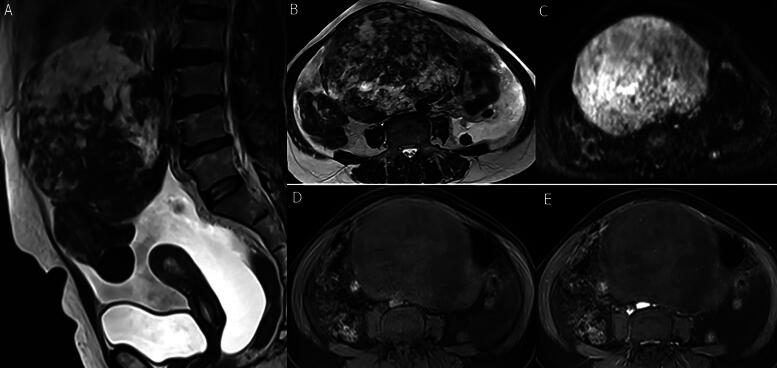

Introduction: Ovarian fibrothecoma is a rare benign sex cord-stromal ovarian tumor sorted under the thecoma-fibroma group. We present an analysis of clinical and laboratory findings and the radiological characteristic features of pathologically proven fibrothecomas in variable imaging modalities.

Methods: A retrospective analysis was done for 88 patients with 90 pathologically proven ovarian fibrothecoma between January 2011 and December 2023 from our center's prospectively maintained database. All the patients underwent preoperative ultrasonography, computed tomography (CT), and magnetic resonance imaging (MRI) scans, clinical examinations, basic laboratory tests, and tumor markers.

Results: The results of Spearman's correlation revealed a statistically significant positive correlation between the largest tumor diameter and serum level. CA 125, the degree of ascites, and diffusion weighted imaging (DWI) signal intensity while the results of point biserial correlation revealed a statistically significant correlation of the largest tumor diameter with the presence of ascites, cystic changes, abdominal enlargement, surgery type, and border type. There were also statistically significantly higher hypoechoic lesions in the smaller tumor group (p = 0.001) but not for isoechoic (p = 0.099) and mixed (p = 0.052). Regarding the MRI, there was a statistically significantly larger tumor diameter in T2 mixed-hyperintense versus hypointense (p = 0.007) and intermediate (p = 0.010) signal intensities.

Conclusion: Fibrothecoma showed a statistically significant positive correlation between the largest tumor diameter with serum level CA 125 and the amount of ascites. On imaging, it shows mild enhancement in both CT and MRI, with a statistically significant positive correlation of the largest tumor diameter with T2 and DWI signal intensity.